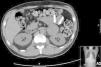

Fez tomografia axial computadorizada (TAC) tóraco‐abdominal que demonstrou ligeiras alterações esclerofibróticas apicais, infiltrados em vidro despolido disseminados, com espessamento dos septos interlobulares, adenopatia subcarinal com 1,5cm de diâmetro, engurgitamento hilar bilateral, derrame pleural bilateral com componente intercisural e massa sólida hipodensa em contiguidade com a glândula suprarrenal esquerda, com calcificação no interior, de limites relativamente bem definidos embora com ligeira densificação estriada da gordura adjacente, medindo cerca de 4,5x5,5cm (Figura 2).